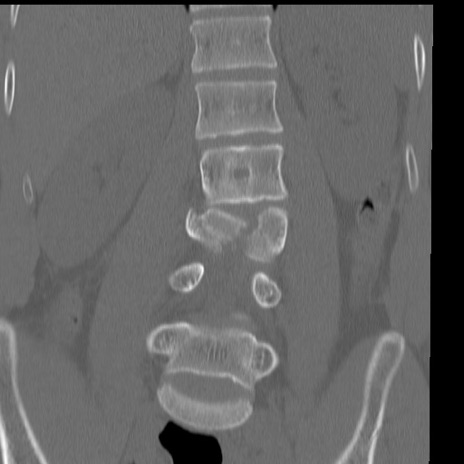

症例3 腰椎CT(冠状断像)

【症例】30歳代男性

【主訴】腰痛

【現病歴】本日旅行先で観光中に、友人と衝突し転倒し受傷。

【身体所見】麻痺なし、右下腿内側前面外側、左下腿内側に知覚鈍麻・しびれ

異常所見と診断は?

腰椎CT